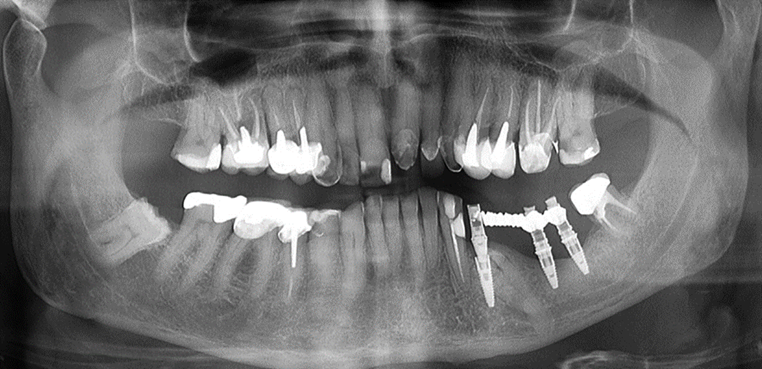

Case 1: a 37-year-old patient sought treatment with osseointegrated implants to replace a removable prosthesis in the posterior region of the mandible. In the imaging exams, a lower premolar was discovered included in the edentulous area (figure 1). After evaluation by an orthodontic specialist, traction was ruled out. In an evaluation using cone beam tomography, a close relationship was observed between the tooth and the inferior alveolar nerve from the crown to the apex, the nerve was embraced by the tooth (figure 2). When assessing the risk-benefit of tooth removal, the high chance of paresthesia was considered, in addition to a probable large height defect after tooth extraction.

Figure 1: Panoramic radiograph showing an impacted premolar in an edentulous area (third quadrant).

Case 2: A 42-year-old patient sought rehabilitation of the bilateral posterior mandibular region. In the imaging exams, impacted premolars were observed on both sides (figure 4). In the detailed tomography exams, it was observed that despite the close relationship between the inferior alveolar nerve and the impacted teeth, in both cases the crown presented a safe distance about the nerve (figure 5).

Figure 4: Periapical radiograph after the period of implant osseointegration and prosthetic rehabilitation.

Case 4: a 38-year-old patient presented a class III maxillomandibular relationship with retention of multiple permanent and supernumerary impacted teeth. The teeth in the mouth were deciduous, supernumerary. Due to the number of impacted teeth and the size of the roots of the teeth in the mouth, orthodontics was contraindicated. Initial treatment was performed using Le Fort I osteotomy for maxillary advancement and bilateral sagittal osteotomy of the mandibular ramus for setback (figure 13). After 6 months under general anesthesia, the teeth in the mouth were removed, and 4 implants were installed in the maxilla and 4 in the mandible, respecting the remaining included teeth with the exception of the implant installed in the region of tooth 21 that transfixed the crown of the one that was included.

Figure 13: Panoramic radiograph after the period of implants osseointegration and prosthetic rehabilitation.